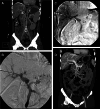

If portal vein stenosis (PVS) occurs within 1 month after liver transplantation (LT), especially within 1 week, it can be catastrophic and result in rapid loss of the grafts and mortality. Although surgical treatments have been considered standard treatment for PVS, patients are usually unable to receive operations or re-transplantations, because of their critical conditions and a shortage of grafts. Recently, primary percutaneous transhepatic portal vein stents (PTPS) were suggested as alternative and less-invasive treatments of PVS. However, because lethal complications may follow these primary stent placements for patients in early stages after LT, primary PTPS placements for patients suffering PVS 1 month after LT has been suggested. From November 2009 to July 2015, 38 consecutive adult patients underwent LT at our institution. Among them, six recipients suffered PVS within 1 month after LT. Technical success was achieved in all six patients. Clinical success was obtained in two of the four patients suffering PVS within 1 week after LT, and in the other two patients suffering PVS>1 week after LT. All surviving patients and their grafts were in good condition, and their stents remained patent. Our experience showed that primary PTPS placements can be used to effectively treat patients with PVS encountered within 1 month, and even within 1 week, after LT with acceptable short-term results. However, possible fatal complications should be kept in mind. Long-term results of these procedures need further follow-up.